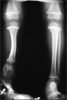

Deformed and shortened leg in a 3 years old child

Congenital fibular hemimellia with proximal lengthening and distal corticotomy to correct procutvatum and valgus at tibia

Length tibia restored with correction of deformity